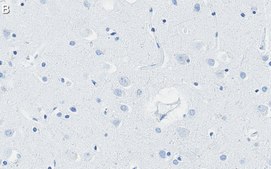

Immunohistochemistry (Paraffin) Analysis: A 1:100 dilution from a representative lot detected Presenilin-1 in human cerebral cortex tissue sections.